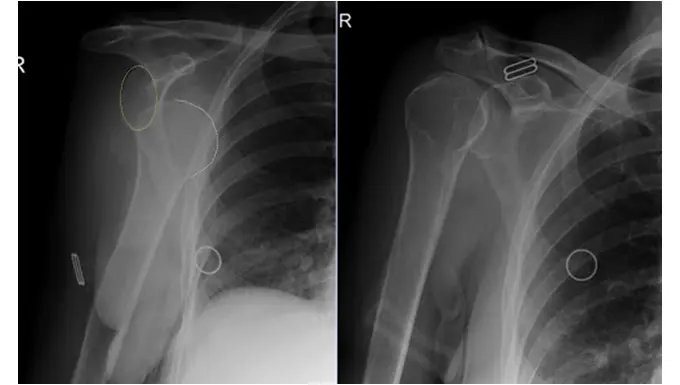

Diagnosis is based on:

- Clinical examination (appearance and limited movement)

- Imaging, usually X-rays, to:

- Confirm the dislocation

- Rule out associated fractures